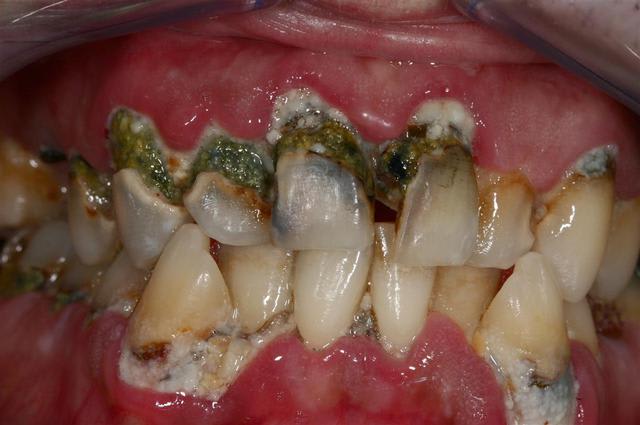

sans avoir l'intention de me moquer, parce que chacun rencontre ses propres difficultés au quotidien, je vous propose d'envoyer vos meilleurs photos de bouche la plus dégueu que vous ayez rencontré.

je commence:

vu ce matin (j'ai encore la nausée, l'odeur est tenace, même avec les fenêtres ouvertes)...

l'assistante; de quand date votre dernier rdv ?

" ho! ça fait un bail, mais comme je n'ai aucun problème je ne viens pas"

moi; et mis à part cette petite douleur qui vous empèche de dormir depuis trois jours, tout va bien ?

" oui, c'est parfait"